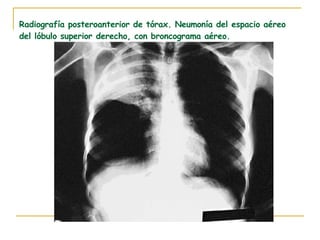

Detalle de radiografía posteroanterior en un paciente con neumonía del lóbulo superior derecho. Imagen de condensación alveolar.

Radiografía posteroanterior de tórax. Neumonía del espacio aéreo del lóbulo superior derecho, con broncograma aéreo.